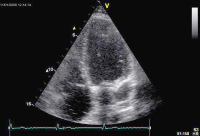

Echokardiographie aktuell: Tubuläre Struktur im Bereich des Sulcus atrioventricularis links bei 2 Patienten

Journal für Kardiologie - Austrian Journal of Cardiology 2009; 16 (1-2): 46-47 Volltext (PDF) Abbildungen mit Filmsequenzen